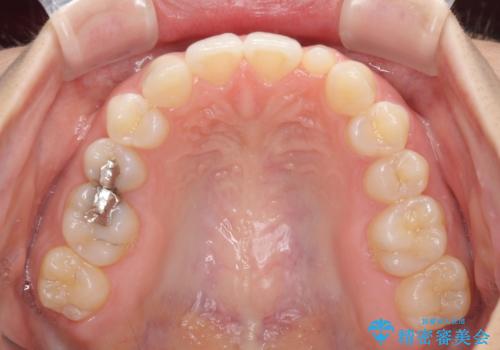

海外転居前に気になる前歯を整えたい 上下前歯の部分矯正

- 1年後に海外に転居するため、気になる前歯を矯正治療で整えたいとのことで来院された患者様です。

下顎は叢生が強かったため、奥歯までワイヤーを装着し、上顎は前歯の一部のみ気になっていたので、その部分にだけワイヤー装置を装着することとしました。

部分矯正は、適応となる症例が限定されます。

こちらの患者様は部分矯正が可能な、非常に珍しい方でしたが、部分矯正を希望される患者様の大半は、全顎矯正が必要となります。

安易に部分矯正を受けると、予想もしていなかった仕上がりとなることがあるので注意が必要です。